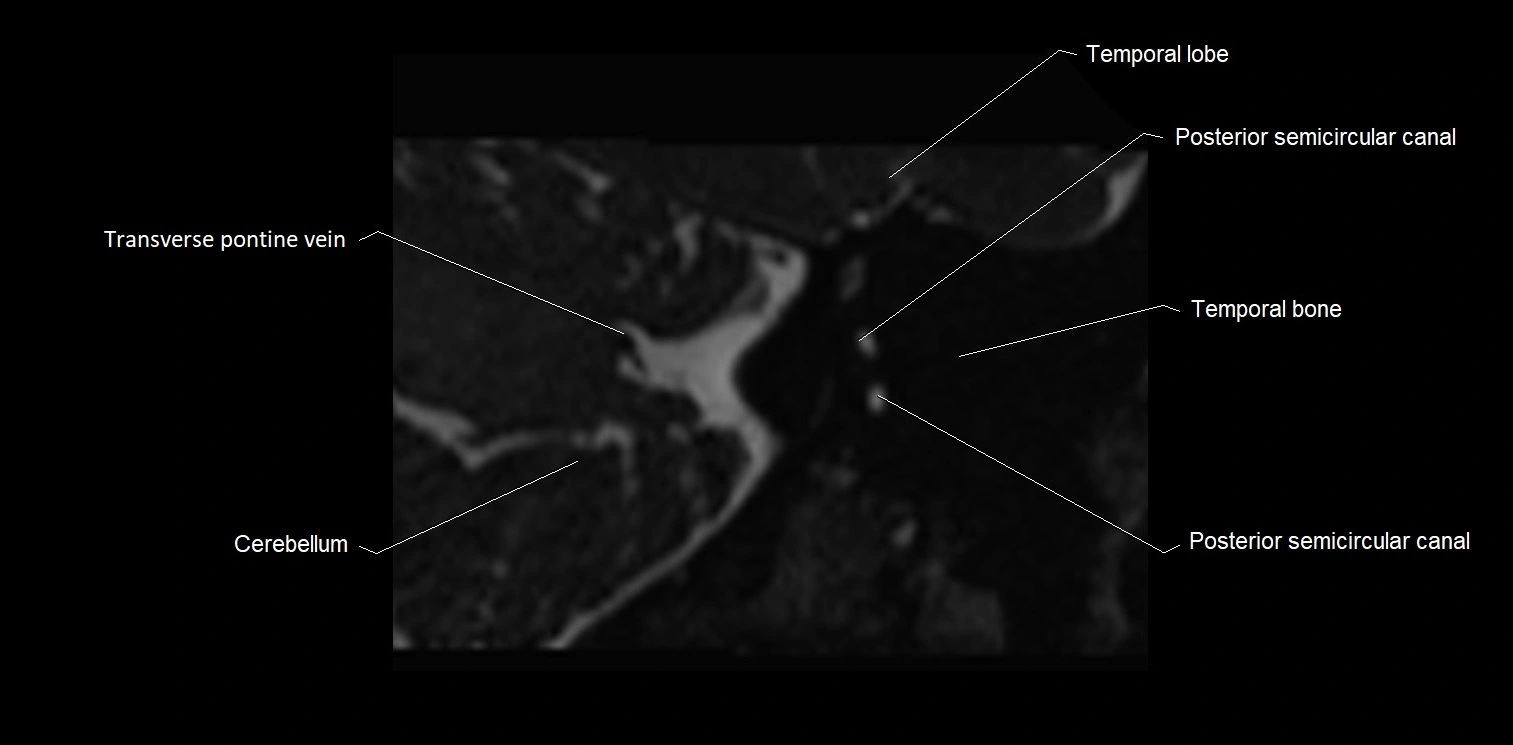

MRI Appearance

• The abducens nerve is a small, thin, linear structure

• Best visualized on high-resolution T2-weighted 3D MRI sequences (e.g., FIESTA or CISS)

• Seen as a hypointense (dark) line running from the brainstem at the pontomedullary junction, traversing the prepontine cistern, and entering Dorello’s canal under the petrosphenoidal ligament, then into the cavernous sinus, and finally the orbit

• May be challenging to visualize in standard MRI due to its small size

• Pathology may be inferred by absence, displacement, or enhancement of the nerve